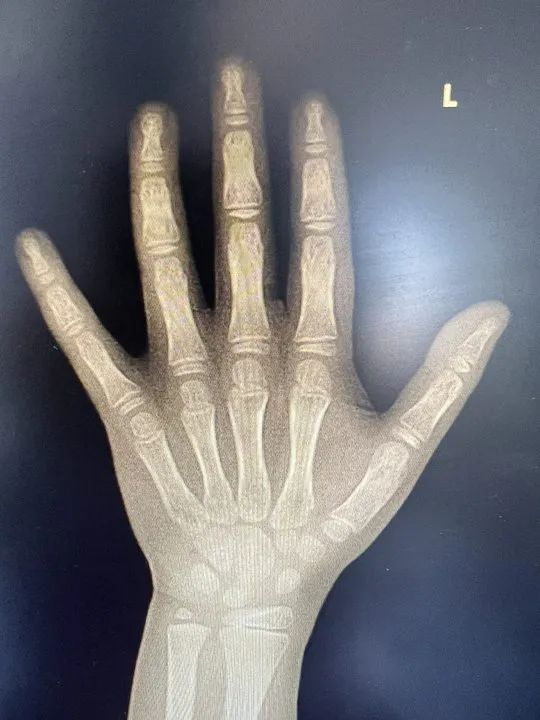

春季助长高,省中儿科送福利啦——免费测骨龄!!!

骨龄是什么,为什么要拍骨龄?

免费测骨龄活动具体安排

活动时间:3月30日(周六) 上午8:30-12:00

活动地点:江西省中医院红谷滩国医堂院区2楼

参与对象:5-14周岁儿童青少年(活动报名前200名)